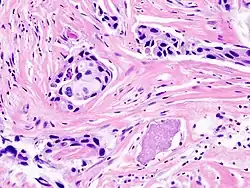

Classification of cancers has been dominated by the fields of histology and histopathology which aim to leverage morphological markers for accurate identification of a tumor type. Histological methods rely on chemical staining of tissues with pigments such as haematoxylin and eosin and microscopy-based visualization by a pathologist. The identification of tumor subtypes is based on established classification schemes such as the International Classification of Diseases published by the World Health Organization which provides codes to classify diseases and a wide variety of signs, symptoms, abnormal findings, complaints, social circumstances, and external causes of injury or diseases. For some types of cancer, these methods are unable to distinguish between subclasses; for example, defining subgroups of diffuse large B-cell lymphoma (DLBCL) have largely failed due to discrepancies between inter- and intra-observer reproducibility.[1] Furthermore, the clinical outcomes of tumors classified as DLBCLs is highly variable[1] suggesting that there are multiple subtypes of DLBCL that cannot be distinguished based on these histological markers. Breast tumor classification too has largely failed based on these predictors.[2] Development of effective therapies depends on accurate diagnosis; additionally, poor diagnosis can lead to patient suffering due to needless side-effects from non-targeted treatments and to increased health care expenditure. Most telling perhaps is that 70-80% of breast cancer patients receiving chemotherapy based on traditional predictors would have survived without it.[3][4]